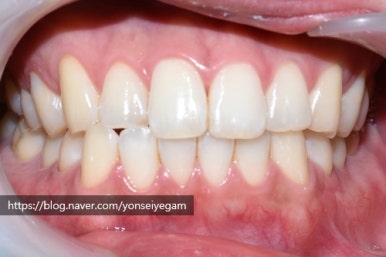

매일 커피를 많이 먹어요

커피를 많이 드신다는 직장인 남자분인데요

1일1커피 또는 그이상하는 분들 많으시죠?

담배를 피지 않음에도 치아가 아래 사진과 같은 모습이었어요.

치료 전 모습으로 치아가 누렇고 착색이 있으며, 치아 패인 부분이 있음(화살표)

구강검진 후 스케일링,치아 패인곳(화살표) 떼우기, 원데이2회미백을 진행하기로 상담하였으며

원데이 2회 미백 후 몇 달 지나고 원데이 미백2회를 더 하길 원한다고 하셨습니다.(커피를 많이 드시기 때문에)

아래는 첫 날 치료(스케일링, 치아패인곳 떼우기, 원데이2회미백 진행)의 전&후 사진입니다.